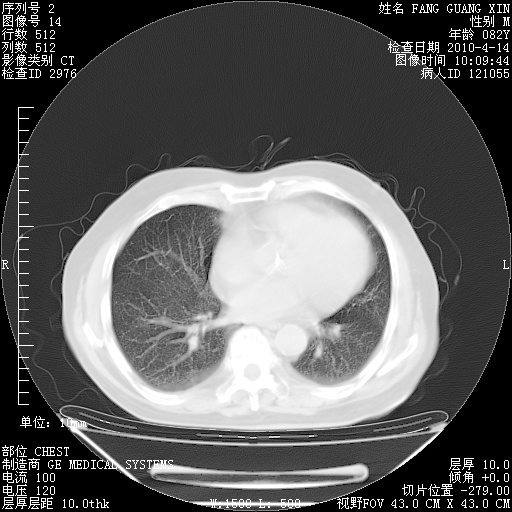

4月28日肺部CT——再次出现类似去年5月9日——透光度降低,(影像科认为)“间质性”改变。

4月28日肺部CT——再次出现类似去年5月9日——透光度降低,“间质性”改变。